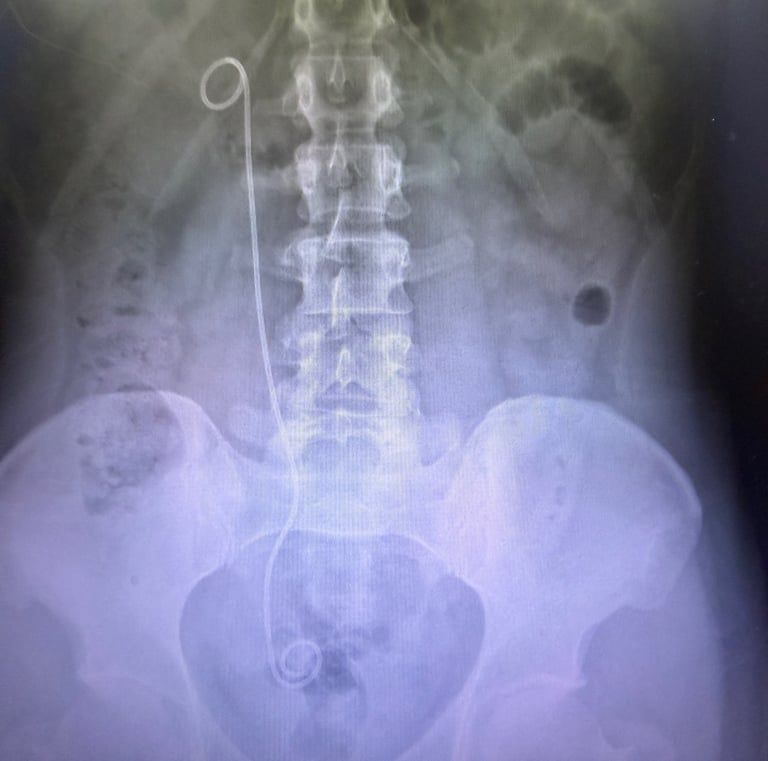

Galería

Imágenes que reflejan cuidado y confianza.